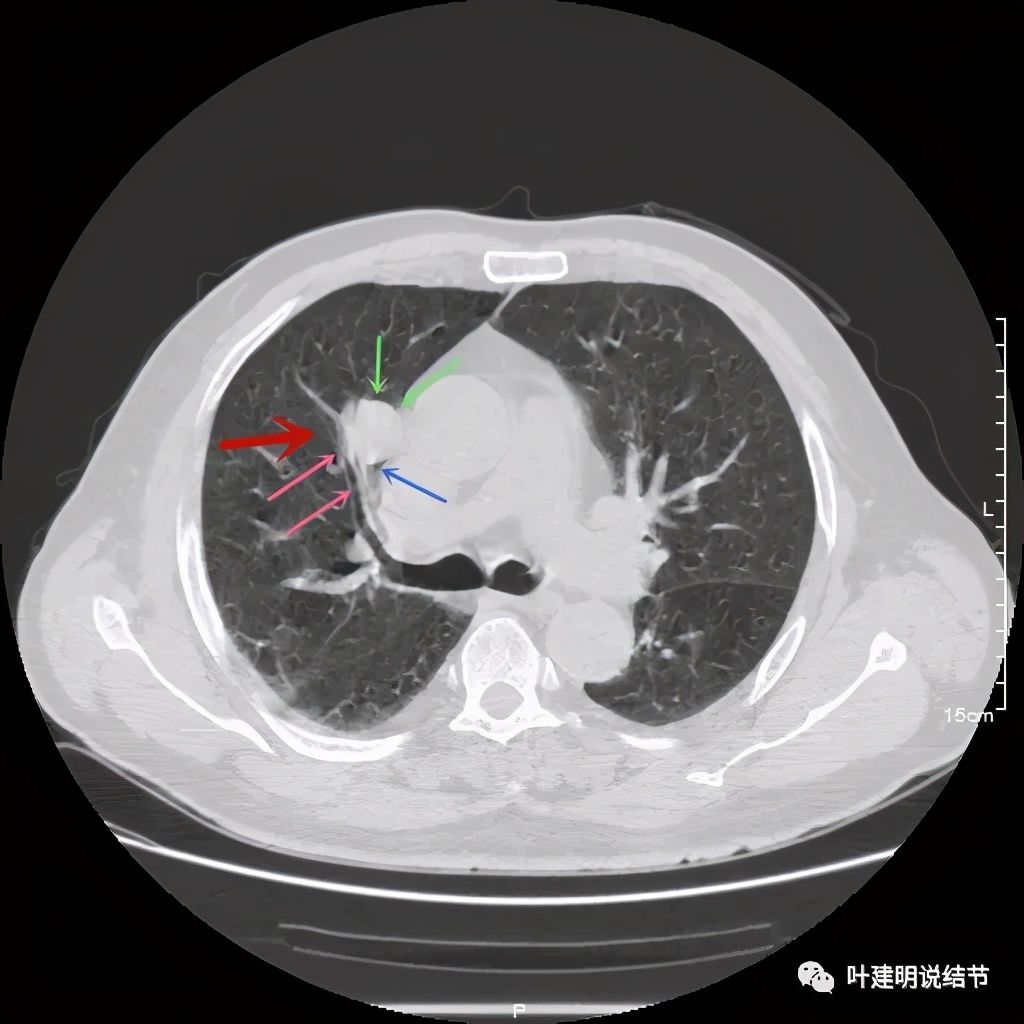

上图示病灶密度不均,但边缘过于光滑(绿色);支气管似有截断(粉色);局部有点状钙化(蓝色)

上图也示病灶密度不均,但边缘过于光滑(绿色);支气管似有截断(粉色);局部有点状钙化(蓝色)

病灶在上图层面似见支气管也是贴壁的。那么增强后又是如何呢?